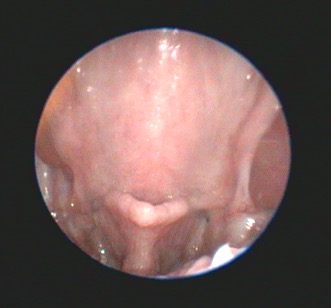

Traditional surgical treatment has largely focused on staphylectomy (soft palate resection) and rhinoplasty (nostril wedge resection). The value of laryngeal saccule excision has been debated, but overall is probably more widely performed than not (Figure 3). With increased availability of advanced imaging modalities and data from WBBP-based research, modifications of multilevel surgery (MLS) with a better outcome compared to traditional surgery include a modified folding flap palatoplasty (Figure 4), rostral alar fold resection and modified alar wing resection (Liu et al., 2017). Depending on the individual patient findings, tonsillectomy and laryngeal procedures (eg resection of everted laryngeal saccules, partial cuneiform arytenoidectomy) may also be indicated. Laser-assisted turbinectomy (LATE) can benefit some dogs, although currently in the UK this would generally be a later surgical procedure performed in refractory animals that may require some concurrent revision of the original MLS procedures. Age, body condition and laryngeal collapse have been found to be the main prognostic indicators for surgery – younger dogs, normal/underweight dogs and those with laryngeal collapse (worse than everted laryngeal saccules) have a poorer prognosis (Liu et al., 2017).